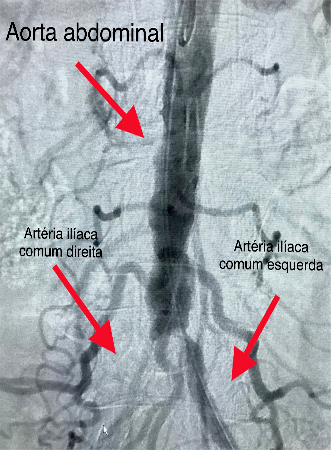

Embolização de Varizes Pélvicas

Varizes Pélvicas é o nome dado para a dilatação das veias localizadas no interior da pelve, próximas ao útero, bexiga e reto. Quando volumosas, essas varizes provocam dor no baixo ventre, dor durante a relação sexual, hemorroidas e varizes na face interna da coxa e períneo. Novas técnicas endovasculares pouco invasivas, permitem o tratamento do problema, com melhora na qualidade de vida desses pacientes.

A embolização de varizes pélvicas é feita através da punção de uma veia superficial do braço. Utilizando cateteres, o cirurgião vascular ocluirá os vasos doentes com liberação de espirais metálicas e substância química na forma de microespuma densa.

As molas em conjunto com a espuma provocarão a oclusão gradual das veias que originam as varizes, levando ao seu desaparecimento.